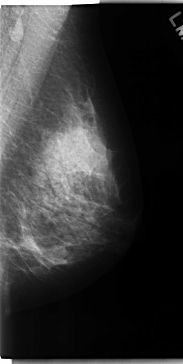

C_0162_1.LEFT_CC

LEFT_CC LINES 4736 PIXELS_PER_LINE 2624 BITS_PER_PIXEL 12 RESOLUTION 50 NON_OVERLAY